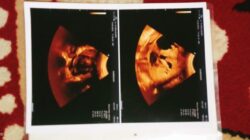

Dia didiagnosa mengidap penyakit kanker di bagian perut. Namun, tak mampu melanjutkan pengobatan karena tidak punya biaya.

Menurut keterangan dokter, penyakitnya kanker. Namun, karena tidak punya biaya, ibunya tidak melanjutkan pengobatan.